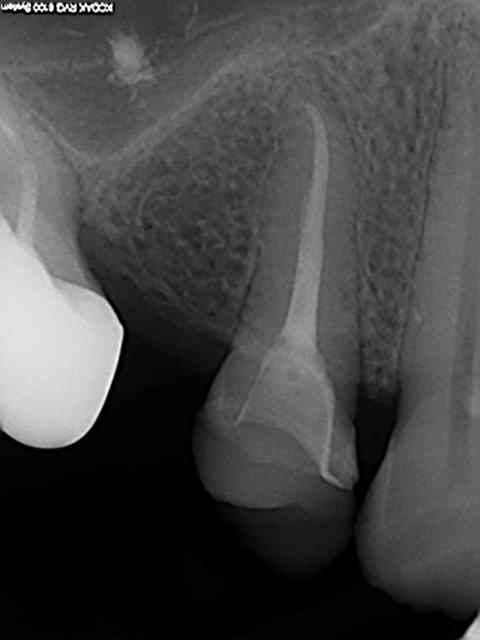

Je vois les choses comme ça: devit. Préparation chambre légère dépouille.je sape les cuspides et parois trop fragiles jusqu'à avoir 1.5mm. En général je me retrouve avec les parois moins 2 3 mm occlusal. Pas de congé. C'est donc très conservateur.

Et je demande une pièce en emax monobloc que je colle.

Esthétiquement c'est très co venable.. je me limite aux secteurs lat et posterieurs pour cette technique. Je cote ça spr50.validé par mon CDC.

Pour l'aspect cotation j'ai été contrôlé récemment sur une quinzaine de cas.

Tout s'est bien passé, sauf justement sur un cas d'endocouronne proche d'un gros onlay: spr50 refusé.

Dans le cas présent, j'ai une prépa périphérique, un collage en exploitant les parois de la cavité d'accès. Donc SPR 50 sans aucun doute. Le but était d'éviter le tenon radiculaire.

Plus qu'un débat de cotation, je voulais surtout montrer l'avantage de lancer la reconstitution définitive avant d'avoir fait le retraitement radiculaire et donc de coller la céram avant la dépose de la digue mise en place pour l'endo.